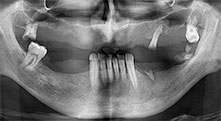

Piezomed B6

La cresta alveolare è stata incisa su entrambi i lati tramite piezochirurgia (strumento utilizzato: Piezomed B6). Gli impianti sono stati posizionati con la stessa procedura e l'osso peri-implantare è stato costruito con la tecnica GBR.

impianti

I quattro impianti sono fissati come programmato. I molari mascellari distali possono comunque essere utilizzati per fissare la protesi in linea introdotta un mese dopo l'impianto.